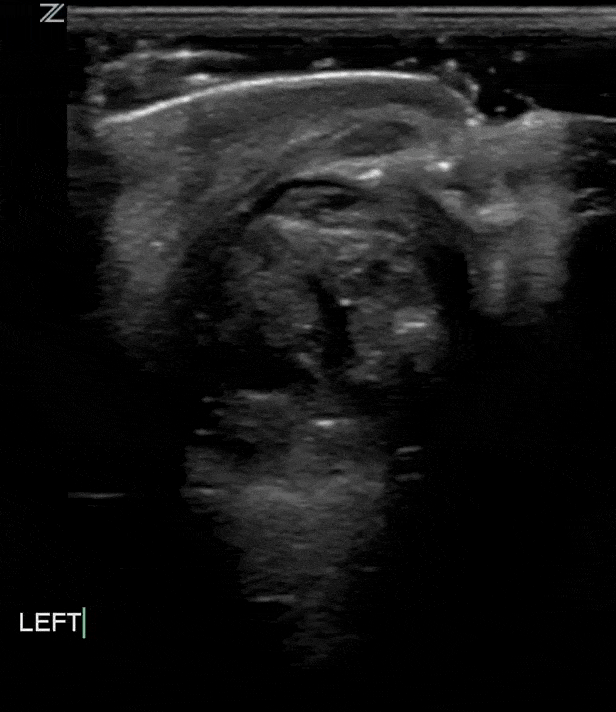

Globe Rupture

Globe rupture often happens in the presence of blunt or penetrating trauma that causes a full thickness laceration or defect of the sclera. Traumatic globe rupture is an emergency.

These patients present with painful vision loss and extrusion of vitreous fluid.

As with rupture of other organs sonographically you may see a heterogenous amorphous complex structure with varying levels of echogenicity. The normal structures like anterior chamber, lens etc may not be easily identifiable. As with other traumatic injuries there may be significant edema or other inflammatory changes of the surrounding soft tissues.